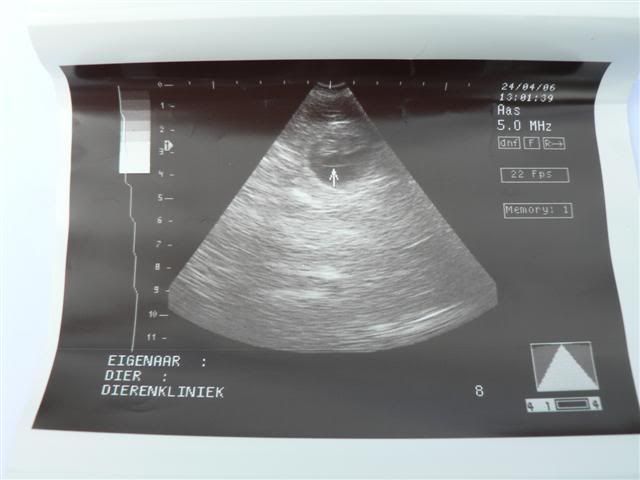

Vandaag, op de sterfdag van Bolletje zagen we op de echo dat Pientje puppies krijgt. Er waren er 5 heel goed te zien. Over het aantal kon ze moeilijk iets zeggen omdat ze verlegen waren en zich achter elkaar verscholen. Het zal geen supergroot nest worden maar de dierenarts verbaast zich nergens meer over......

Pien is op 27 mei uitgerekend, dat is dan 63 dagen na de 2e dekking.